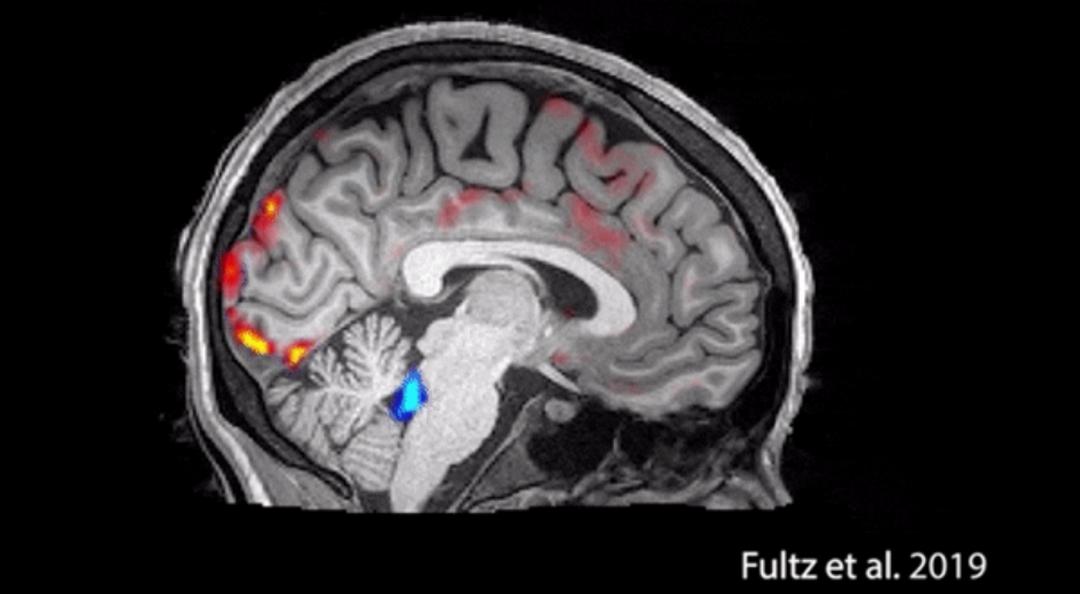

来看一张图:

在图片里,红色的代表血液,蓝色的代表脑脊液。

平常我们睡觉的时候,大脑并不需要太多氧气,血液会周期性地流出大脑。

此时,大脑内压力降低,脑脊液便会趁虚而入,清扫脑细胞的代谢物。

可是,如果频繁熬夜,脑脊液就无法顺利进入大脑,清扫“废物”了。